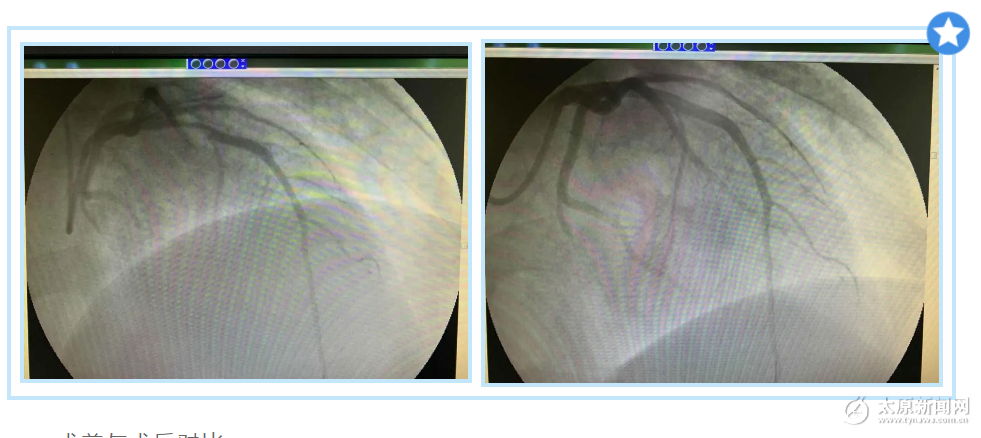

術前與術后對比

雖然患者恢復心跳,可以自主呼吸,但進一步檢查發現情況不容樂觀,患者出現血壓低、血管堵塞,需要進行血管造影手術,他們嚴格按照我院疫情期間手術的管理要求,迅速投入到緊張的手術之中。

造影完畢,證實了醫生的判斷,患者的冠狀動脈血管完全閉塞了,隨后醫生通過球囊擴張將他的血管打通。至此手術結束,患者的胸痛也緩解了,病情轉危為安。目前,患者情況穩定,心跳逐步平穩。